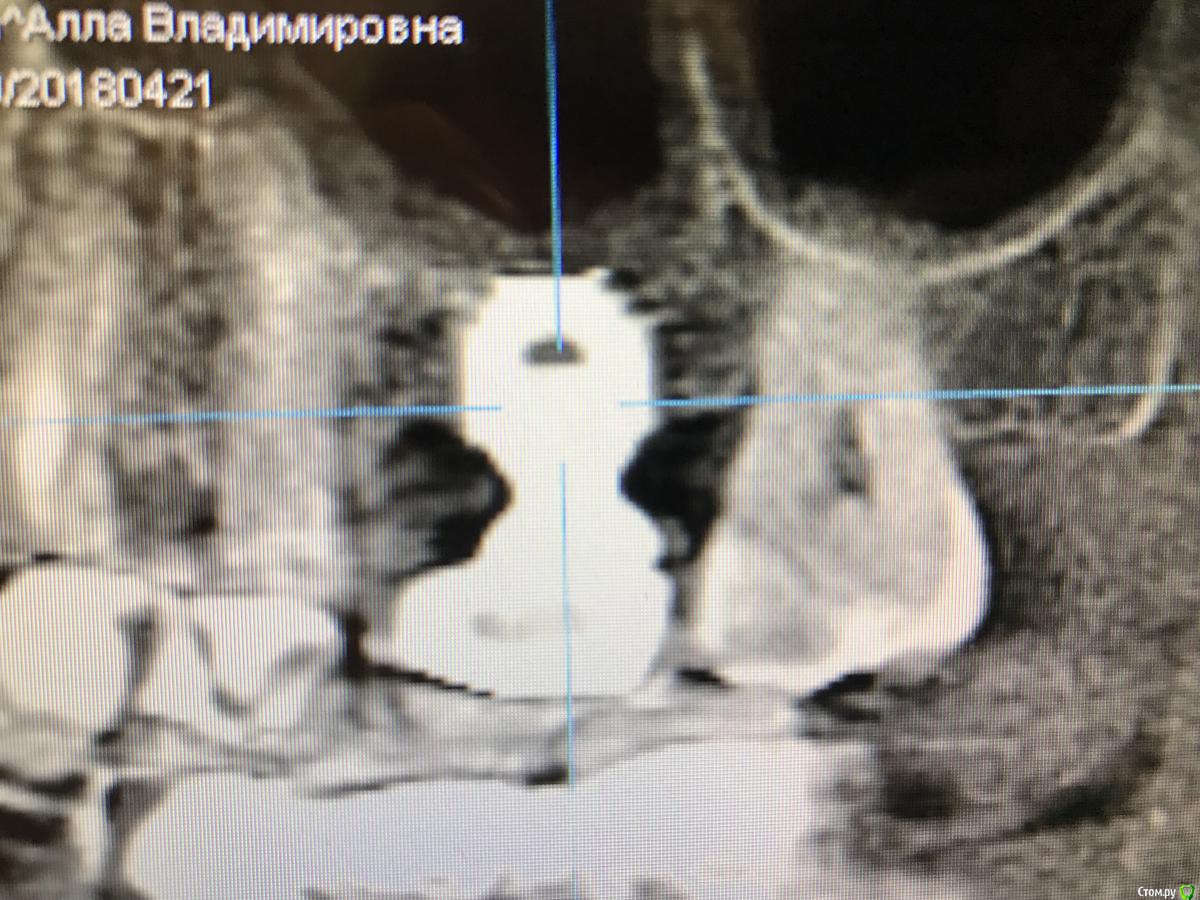

sole13 Опубликовано 5 мая, 2018 Автор Поделиться Опубликовано 5 мая, 2018 (изменено) уважаемые врачи, спасибо за мнения! решила выложить 3-4 снимка до финального момента,возможно, это будет полезно другим пациентам.------------------ вчера была имплантация, в силу моих ограничений временных был доступен врач,практикующий на Нобеле, поэтому с астрой и рекомендациями не сложилось установлен нобель коникал конекшен (pmc) 10 на 5 мм с закрытым синус лифтингом и формирователем сразу же. назначены стандартные антибиотики и противоотечные.на втором этапе через 3-4 месяца договорились решить про десневую пластику,далее временная коронка на 2-3 месяца и постоянная.врач говорит что скорее всего коронка будет выше остальных,но я надеюсь на десну и незаметность. пластику кости доктор, к сожалению, сказал что не сделает в моем случае одномоментно остео синтетическими материалами,только долго и дорого с куском своей кости и т д. перед началом операции врач предупредил что 50 на 50 закрытый или открытый синус, удалось с закрытым в моем случае. вся операция длилась 25 мин: сначала разрезали,потом посверлили ,потом постучали молотком, потом еще посверлили, потом попросили надуть щеки с зажатым носом,чтобы проверить отсутствие перфораций,потом имплант, формирователь и сами швы. потом снимок и принудительно 2 укола внутримышечно дексометазон и антибиотик, лед в руки и отпустили домой. Изменено 5 мая, 2018 пользователем sole13 1 Ссылка на комментарий

sole13 Опубликовано 10 августа, 2018 Автор Поделиться Опубликовано 10 августа, 2018 (изменено) уважаемые хирурги, прошу ваш совет 3 месяца назад было сделана имплантация 26 зуба, закрытый синус,сделано повторное свежее КТ через 3 месяца у меня ощущение постоянного комка слизи в носоглотке с момента операции (иногда отплевывается часть и это оч густое содержимое). пила 2 курса синупреда, 2 месяца на море, 2 курса ринофлоимуцила прокапала. если чуть заболеваю, то слева ощущение тяжести в крыле носа как при гайморите. хирург говорит, что перфорации гайморовой нет и в 50% случаях это нормальная реакция гайморовой - выделять слизь, что через месяца 3-4 у меня это пройдет. действительно гайморова пазуха не перфорирована и ощущение слизи -норма? еще меня смущает черная область вверху импланта справа на снимке и черное под имплантом и справа по вертикали - что это? Изменено 10 августа, 2018 пользователем sole13 Ссылка на комментарий